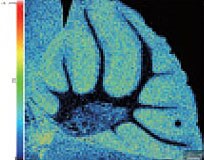

Applications are being studied using an analysis platform and images from an optical microscope and MS imaging system.

Imaging Mass Microscope